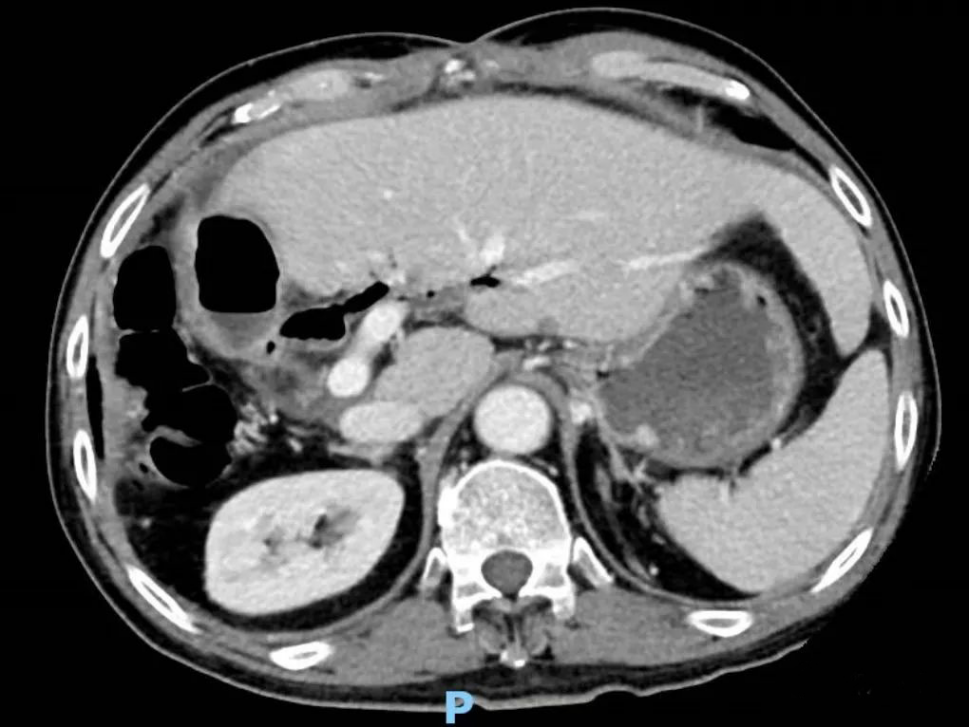

此外,患有慢性乙肝多年的黄先生日前也因为肝区疼痛来院就诊。入院前,黄先生肝区不适,在外院进行肝脏CT检查显示,肝脏肿瘤巨大达20cm,伴有肝硬化、脾大、肝门淋巴结肿大、少量腹水。因病情复杂,从外院来到柳州市人民医院综合外科移植病区住院治疗。

完善相关检查后,医生将影像学资料进行数字化解剖重建,模拟肝切除后计算残肝体积、标准肝体积。经肝癌MDT团队充分讨论,一致认为不具备一次根治性切除条件,可以考虑分期肝切除,并制定了完善的诊疗方案。医生先为患者进行抗乙肝病毒治疗、调整内环境、纠正低蛋白血症等,一周后,团队再次评估发现,患者的肝功能已经从B级好转为A级,但因切除肿瘤后的残肝体积不足,存在发生小肝综合征的风险。将病情与家属充分沟通后,家属同意接受分期肝切除方案。

鉴于病人的情况特殊,为了减轻手术创伤,团队决定采取腹腔镜微创手术实施一期手术。手术团队依序实施腹腔镜下结扎门静脉右支、离断肝实质,手术十分顺利。两周后医生复查肝脏CT并评估肝再生情况,因残肝体积未达到二期肝切除标准,经过MDT团队讨论,给予介入、药物等治疗。1个月后,患者回到医院复查,经团队评估达肝切除条件,再次通过腹腔镜手术顺利切除右肝三叶。术后患者恢复良好,目前已康复出院。